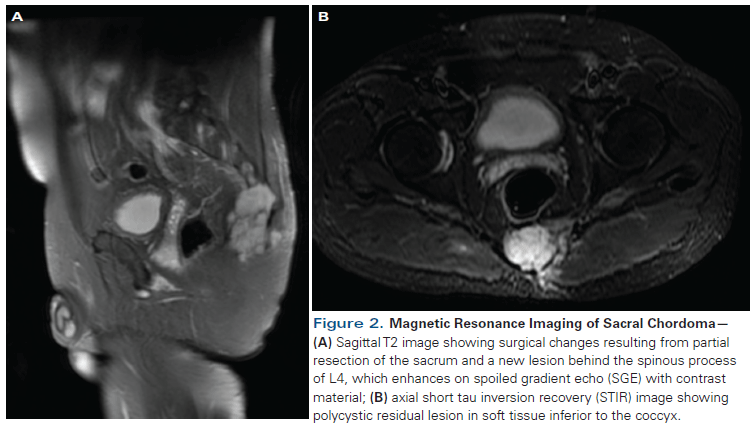

Figure 2. Magnetic Resonance Imaging of Sacral Chordoma

He was lost to follow-up. Six years later, he presented with a 2-cm mass in his left buttock; magnetic resonance imaging (MRI) showed progressive disease of the sacral lesion (Figure 2). He underwent a radical sacrectomy. The pathology revealed a 12 × 7-cm chordoma with infiltration to the sacrum and positive surgical margins (Figure 1C). He received a second course of radiation therapy. Two years later, he had an acute spinal cord compression (at T6–T8, with sensory loss). MRI showed a metastatic lesion on the spinal process and pedicle of the T4 vertebra (Figure 3A). He received palliative radiation to the thoracic spine and laminectomy of T3–T4, with T5 nerve root resection. The pathology examination confirmed the presence of metastatic chordoma.